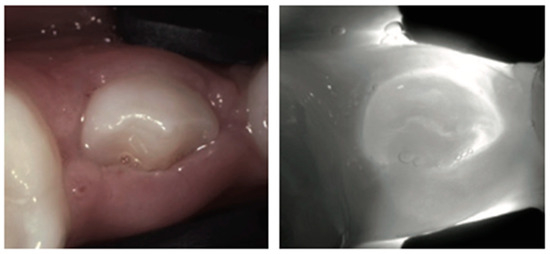

4. Enamel Defects